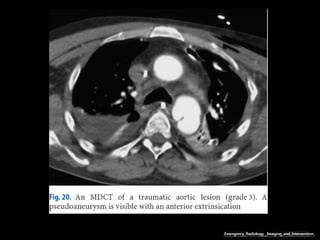

Pseudoaneurisma pós-traumáticos

Segundo tipo mais comum de aneurismas,

envolvendo a aorta torácica e a principal causa de

aneurismas em jovens.

Configuração sacular;

Resultam de transecção parcial da parede e

apresentam expansão com o tempo;

O istmo aórtico é o principal segmento envolvido

em cerca de 90% dos casos;

Pseudoaneurismas pós-operatórios.